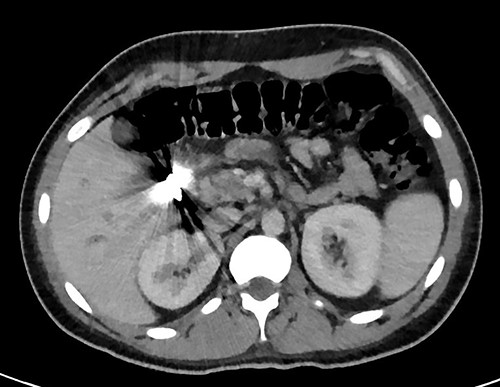

A full lab panel was ordered and revealed a total bilirubin of 1.1, direct bilirubin 0.5, lactate dehydrogenase 196, alkaline phosphatase 80, aspartate transaminase 46 and alanine transaminase 58. A computed tomography (CT) angiographic scan of the chest, abdomen and pelvis revealed the presence of a rim enhancing fluid collection in hepatic segment V with internal gas and containing a metallic foreign body, measuring 8 × 5 cm and consistent with abscess formation (Figs 2–4). The linear tract of the bullet in the right iliac crest was visualized in the CT as well.

Transverse plane of the CT showing the hepatic collection measuring 8 × 5 cm.